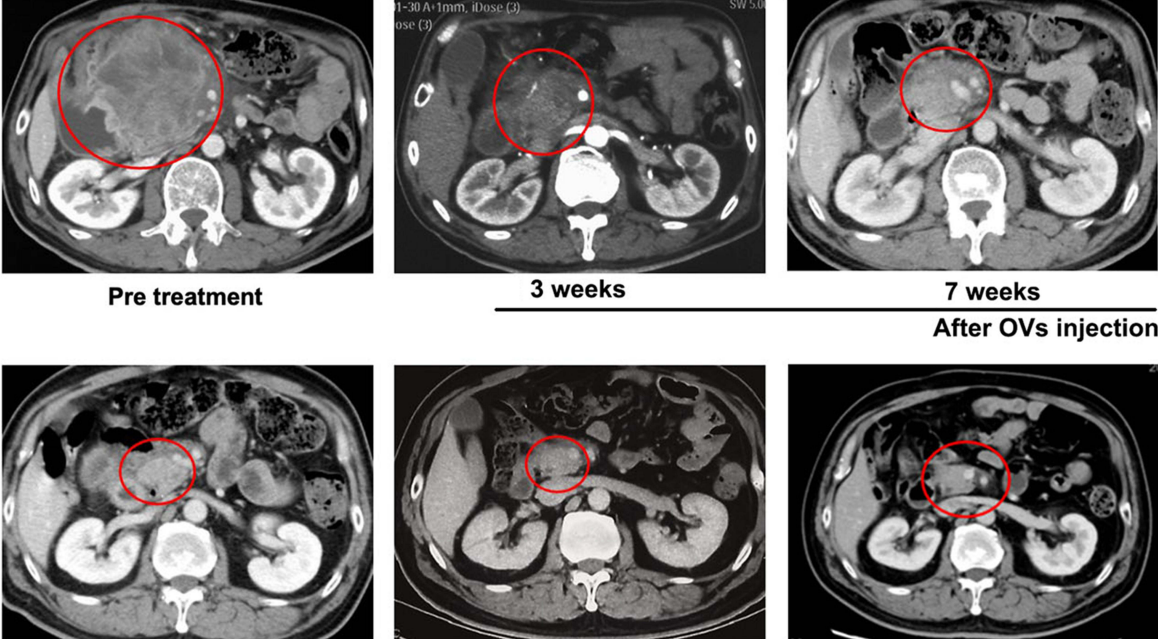

2024年7月,我国研究人员分享了一例结直肠癌巨大淋巴结转移经瘤内注射溶瘤病毒H101联合卡培他滨治疗后达到病理完全缓解的病例报告。

该患者为一位50多岁男性,2020年11月因右半结肠癌接受手术,术后未接受辅助化疗、靶向或免疫治疗。2022年2月起,患者出现体重下降、乏力、腹痛、食欲减退等全身症状,6月CT检查发现腹部一枚直径12厘米的巨大淋巴结转移灶,经活检确认为肠腺癌复发。考虑到患者对系统性治疗副作用的担忧,最终选择瘤内注射溶瘤病毒H101联合卡培他滨的治疗方案。

患者在首次瘤内注射溶瘤病毒H101后3-5天即出现腹痛缓解和体位改善,第二次注射时肿瘤质地已明显变软。治疗3周后(2022年8月8日),CT显示肿瘤从12厘米缩小至4.5厘米,之后持续退缩,至第18周(2022年11月29日)几乎消失。截至2024年2月随访,无复发,无进展生存期达19个月。

肿瘤标志物CEA和CA19-9也显著下降并恢复正常。根据RECIST标准,患者达到完全缓解(CR)。主要副作用为一过性发热(最高39°C),物理降温后可缓解。患者对治疗效果满意,整体状态良好。